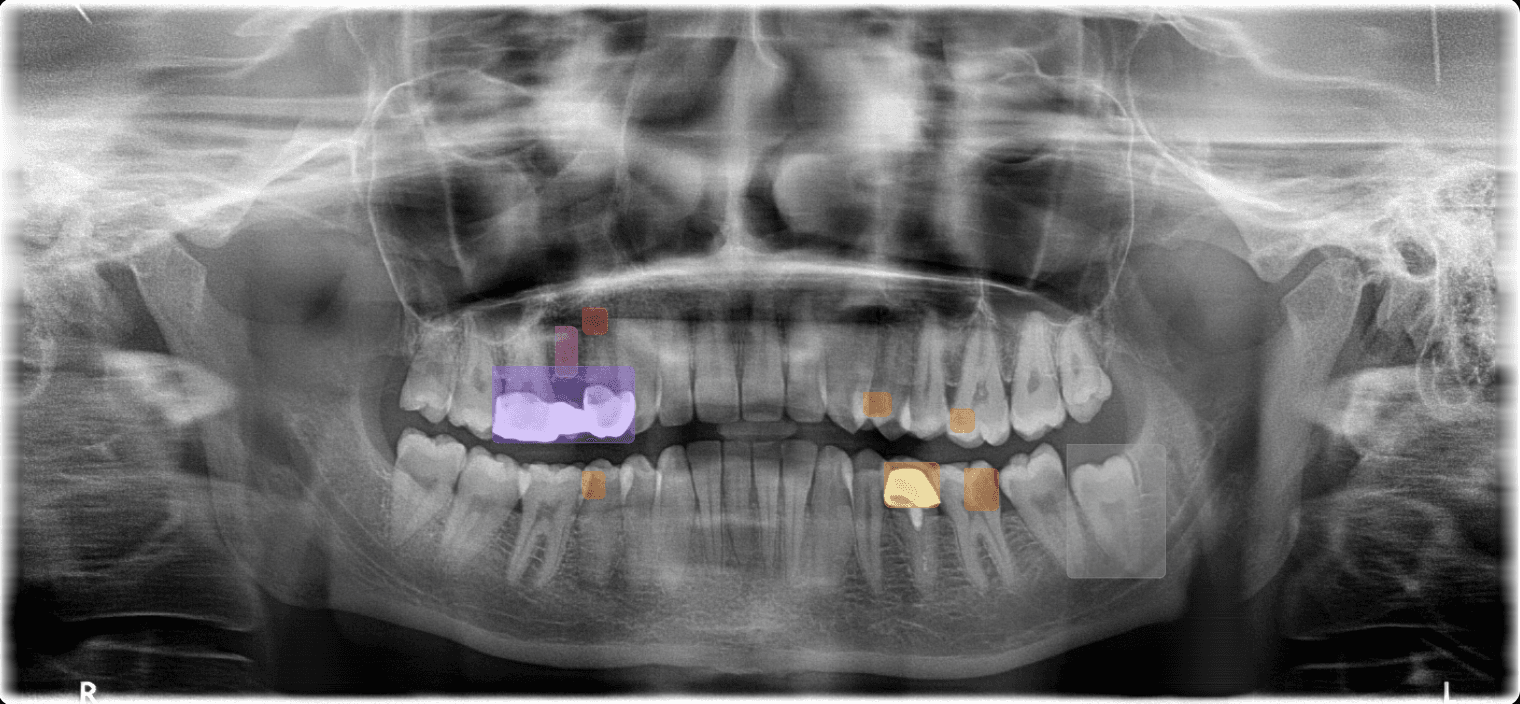

AI X-ray Analysis

AI-powered radiograph analysis that catches what human eyes might miss.

Automatically detect pathologies, number teeth, and track bone loss in seconds. Our AI catches what human eyes might miss.